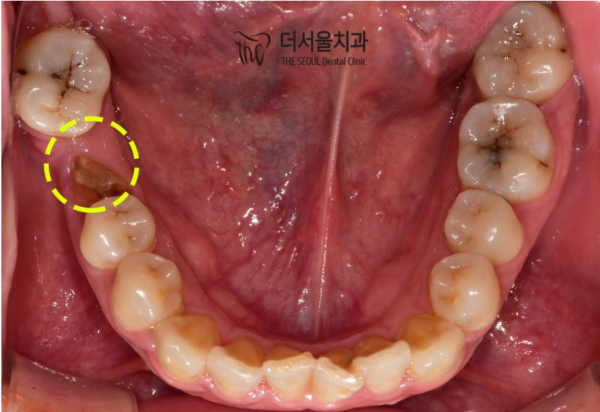

그리고 이렇게 보면, 충치와 어금니가 하나 빠져있는것을 확인할 수 있습니다.

해당 어금니도 충치로 인해 부러지셨다고 하시는데 인접한 어금니가 돌아가 있습니다.

이 환자분의 경우 치아교정을 한 후에

임플란트를 통해 해당 부분을 채워주고

충치치료를 병행하기로 하였습니다.

And if you look at it like this, you can see that there's a cavity and a molar missing.

It is said that the molar was also broken due to a cavity, but the adjacent molar is turned.

For this patient, after getting braces

Fill in the area with implants

I decided to do cavity treatment at the same time.